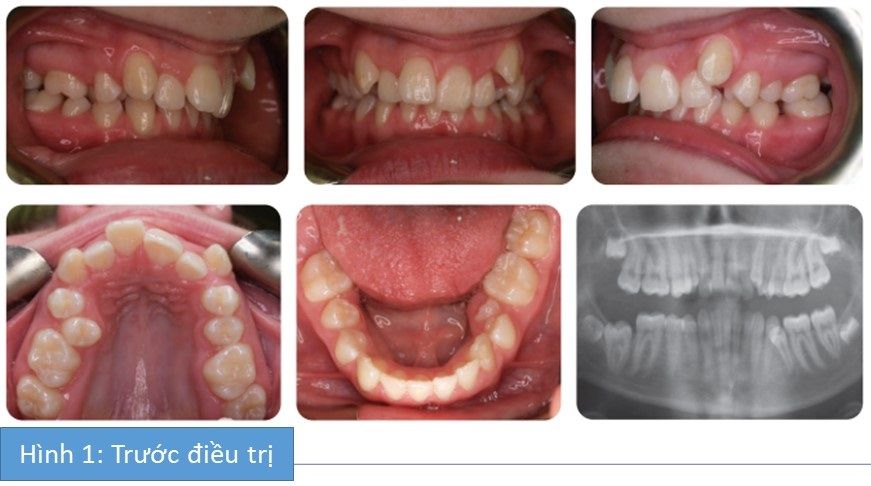

Bệnh nhân nữ 14 tuổi bị sai khớp cắn hạng II tiểu loại I trên nền xương hạng II trung bình với tỉ lệ theo chiều đứng giảm. Có tăng độ cắn chìa, cắn trùm tăng và hoàn toàn, và chen chúc nghiêm trọng ở cả 2 cung hàm. Tương quan răng hàm hạng II 2 bên và bị lệch đường giữa.

- Chen chúc nặng ở cung hàm dưới, R35 mọc 1 phần, R47 chưa mọc

- Các răng cửa dưới nghiêng trong và cả 2 răng nanh nghiêng xa

- Chen chúc nặng ở cung hàm trên. R15 mọc ra ở phía khẩu cái và cả 2 răng nanh hàm trên chen chúc phía ngoài.

- Độ cắn chìa tăng 9 mm (R11) nhưng R21 nghiêng trong.

- 2 răng nanh hàm trên nghiêng gần.

- Tương quan răng cửa là hạng II tiểu loại I với độ cắn chìa lớn ở R11.

- Tương quan răng hàm là hạng II 2 bên

- Đường giữa hàm dưới lệch trái và đường giữa hàm trên lệch phải do chen chúc răng.